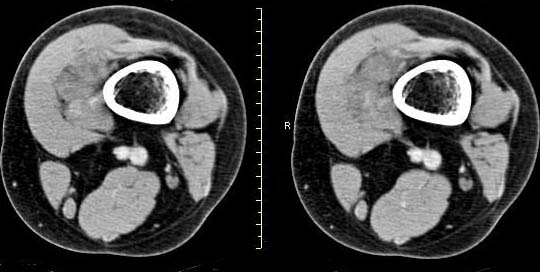

女,24岁,左大腿下部近膝关节处偏内侧有一软组织包块,触之有压痛,平扫示病灶密度不均,形态及轮廓欠规则,无包膜,与周围组织界限不清,增强后显示有明显强化且不均匀强化,本人考虑为该软组织肿块为恶性病变。请大家发表高见!

病理结果:血管瘤。